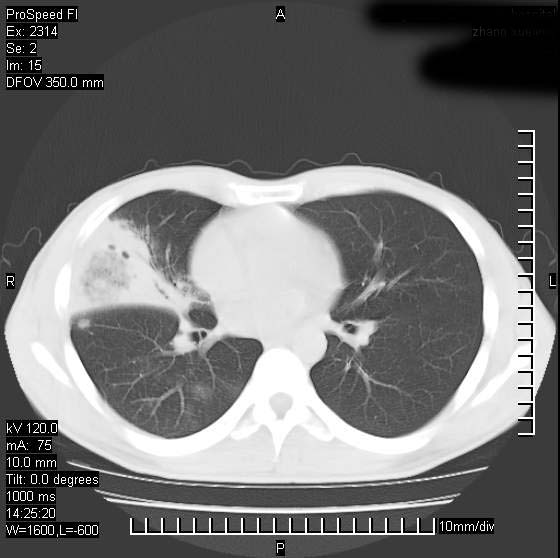

男性,再生障碍性贫血,入院前发热10天,最高40c,右侧胸痛,外院ct示右上,中肺边缘模糊的球性影(就是我现在图中标示的范围),考虑炎症,在我院使用头孢呋辛,洛美沙星10天,高烧消退,自感下午稍有发热,但今天ct示右上,中肺病灶明显扩大,还是考虑炎症,看其中的球型影是否霉菌感染??,是否能排除结核?

右肺中叶外侧段病变,上缘界限不清,下缘锐利,以段性发病为主,内见巨大空洞及空洞内容物,结合病史首先考虑:化脓性肺炎。不除外霉菌感染!

片状高密度影内见空洞影,内可见球形软组织密度影,并有新月征,考虑霉菌感染.